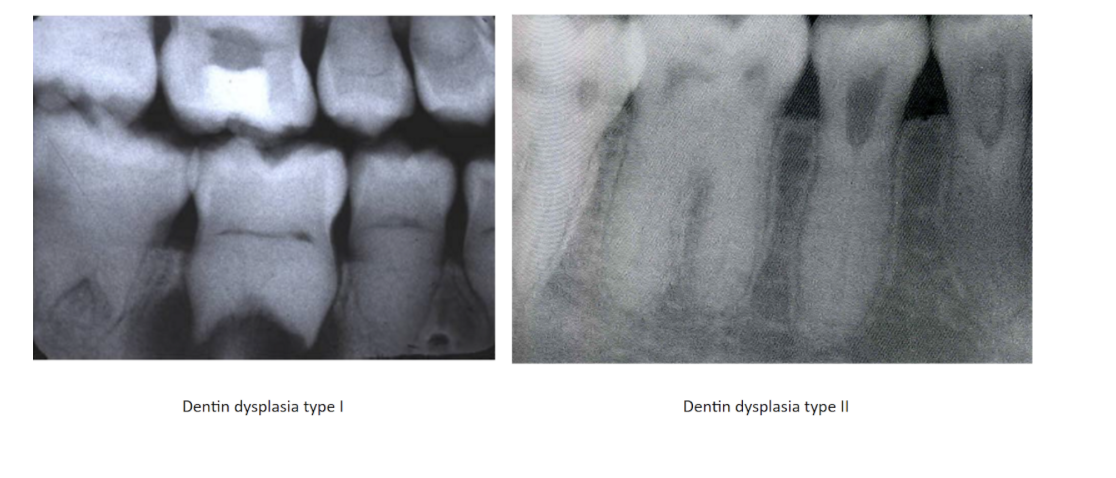

Dentin Dysplasia

Intrinsic alteration of dentin in permanent & primary teeth

Autosomal Dominant

2 types:

* Type 1: Chevron Pulp w/short roots

* Type 2: Thistle shaped Pulp w/normal roots; Primary teeth=blue or amber color

Tx: Not good candidates for restorations

* abnormal dental and pulp morphology

Type 1(radicular): Chevron pulp, minimal root development

Type 2: (Coronal): Thistle tube shaped pulps, normal root

* primary teeth= bluee/amber discoloration

Tx: Endo to keep primary teeth